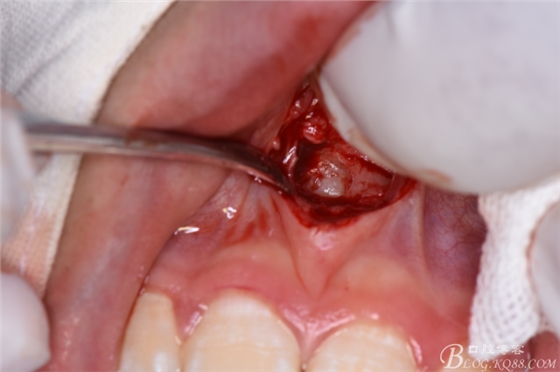

圖20. 在12、13根尖所對應(yīng)的前廳溝處做第二個弧形切口

圖21.一定要切透粘骨膜。

圖22.翻瓣、暴露骨面